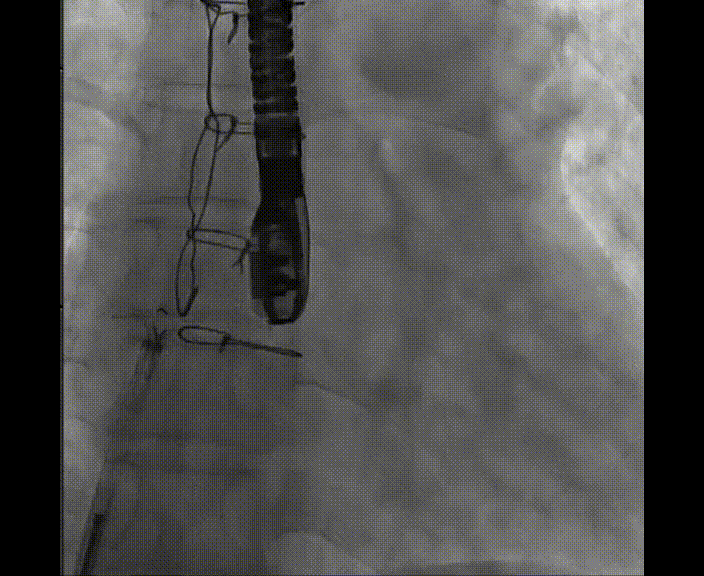

術中首先在局麻下穿刺股動脈、股靜脈,完成心導管檢查評估后轉為全麻,在食道超聲引導下穿刺房間隔,穿刺成功后將加硬導絲送入左上肺靜脈建立軌道,根據患者病情行球囊預擴張后植入6mm孔徑房間隔造孔支架,經透視及食道超聲評估支架左右盤展開良好,夾持于房間隔兩側,固定穩(wěn)定、位置良好,食道彩超顯示房水平右向左為主分流,分流孔直徑符合預期大小,心導管檢查評估達到預期效果,釋放造孔支架。術后12h患者下床活動,恢復順利,擬于近日完善術后評估后出院。